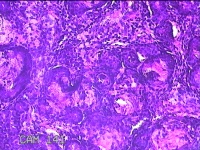

左侧鼻腔病变组织

性别

男

年龄

28岁

临床诊断

1.慢性鼻窦炎 2.鼻中隔偏曲 3.变应性鼻炎

一般病史

反复鼻塞10余年,加重伴脓涕3天。

标本名称

大体所见

灰白暗红色组织0.8x0.3x0.2cm一块,表面糜烂,内有少许骨质。